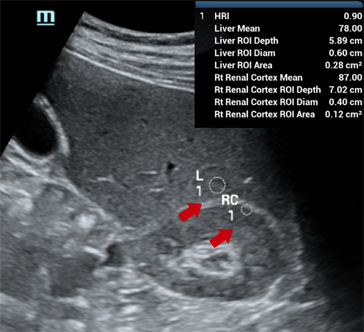

EvaluaciĂłn inteligente de la esteatosis hepĂĄtica mediante el cĂĄlculo automĂĄtico del brillo del hĂgado con la corteza renal en modo B.

CompensaciĂłn de respiraciĂłn

CompensaciĂłn de respiraciĂłn